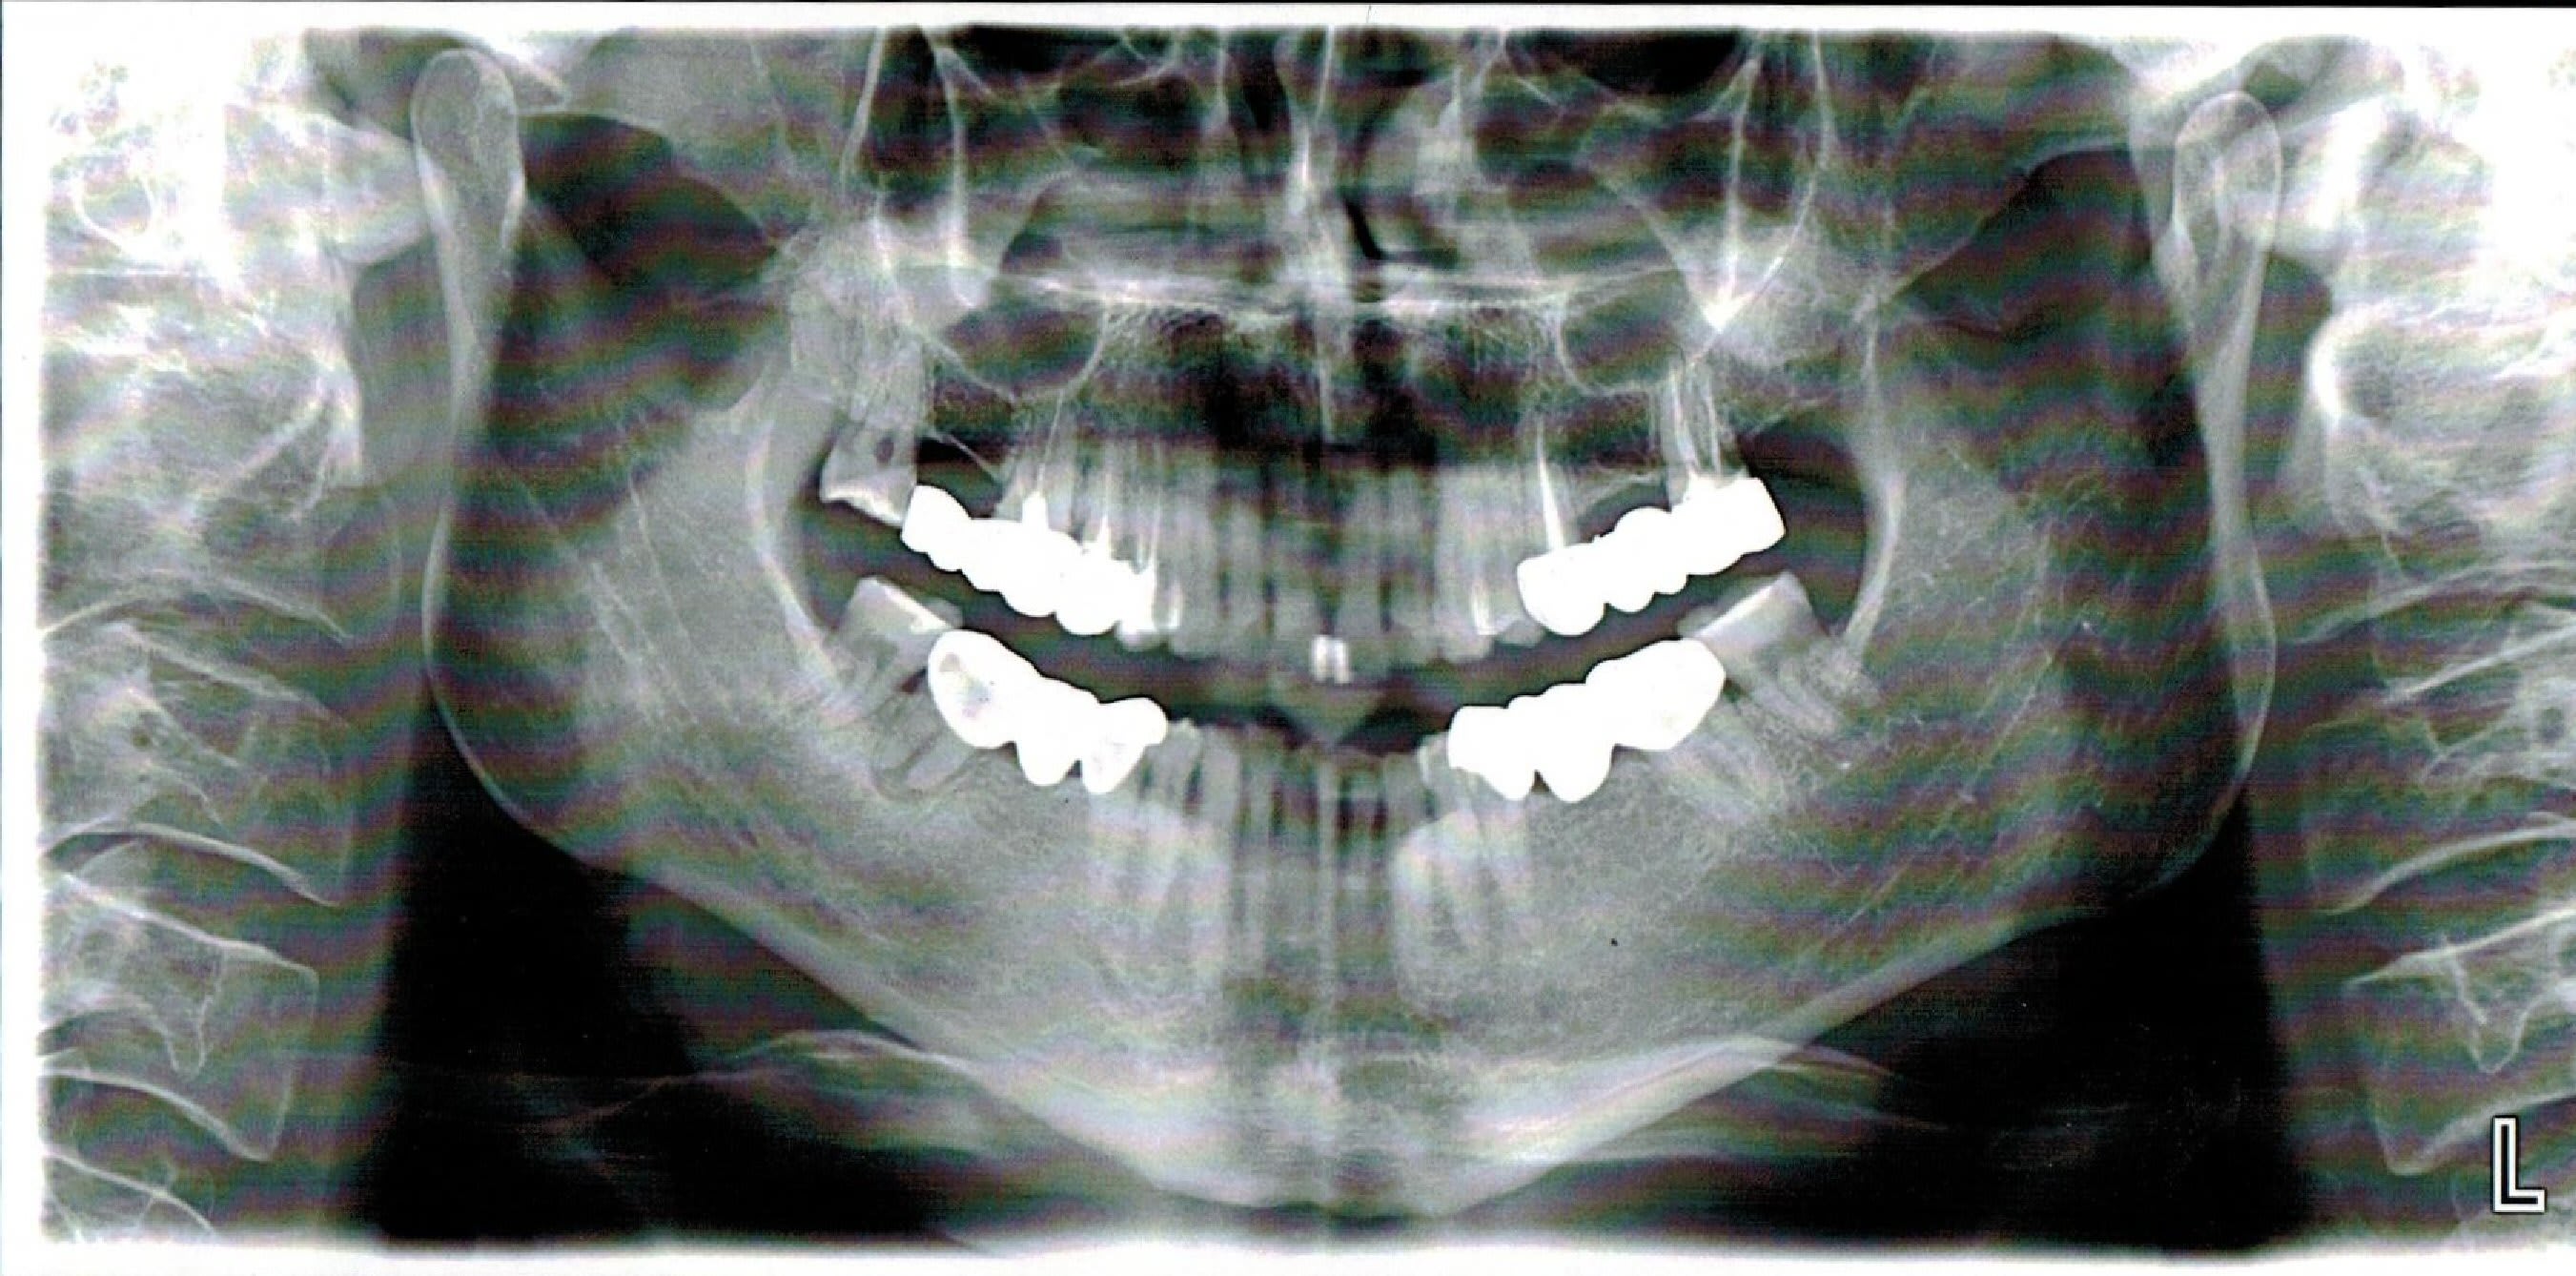

Un patient qui souffre depuis environ 1 an, une a deux fois par semaine le soir vers 17-18h de grosses douleurs diffuses non pulsatiles (maxillaire sup gauche, sinus, oeil, derriere le crane, bref toute la partie gauche mais le centre de la douleur est selon lui localisé au dessus de la 24/25).

Bref, je me suis dis que ca devait venir de 25 ou 27, donc j'ai repris les deux traitements dans les règles, mais aucune amelioration, il y avait aussi une petite carie sur la 24, mais de la a avoir de grosses douleurs pendant 1 an j'y crois pas trop.

Au passage je vous poste le scan réalisé:

L'image plus visible ... qui objective aussi une fracture de la racine Distale de 27.

Tu dis dans ton poste que tu as repris les traitements du secteur 20 pour ensuite dire que le bridge a une vingtaine d'années. Comment as tu fait ds ce cas pour entreprendre une rte sur 27 avec apparemment un inlay core ?... Ce que je vois sur ta pano c'est surtout 2 fractures radiculaires: une au tiers coronaire de la racine mesio vestibulaire juste à l apex du tenon l autre au tiers apical de la 25...sans parler de la grosse lésion sur la racine distale qui ressemble plus à une énorme carie sous la couronne qu'à une résorption externe.

Peut etre pour 25 un artefact? (variation brutale de densité liée au modelé osseux)?

EDIT: en regardant bien, la solution de continuité radiculaire me parait bien importante pour un artefact. La probabilité de fracture horizontale au tiers apical radiculaire est importante!

Oui je suis d'accord j'ai regardé à plusieurs reprises et c'est plus de l'ordre de la fracture ;autant sur 25 que sur la 27. Les piliers du bridge en l'état ne sont plus conservables. Pour le moment cela se manifeste par des douleurs mais d'ici quelques temps d'autres symptômes s'en suivront notamment lorsque la 27 va commencer par lâcher il va apparaître un abcès en vestibulaire juste en regard de la racine mesio vestibulaire ou peut-être en regard de l'espace inter radiculaire et non au fond du vestibule. C'est l'affaire de quelques mois. Il vaut mieux temporiser jusque là et confirmer le diagnostic. Auquel cas il faudra tout déposer et envisager l'extraction des 2 piliers.

Alors il est vrai que la pano est trompeuse mais:

Il n'y a pas d'IC ni sur la 25 ni sur la 27, et pour reprendre les traitements j'ai pu deposer le bridge a l'arrache couronne (je sais c'est pas bien mais sinon fallait flinguer le bridge et monsieur avait pas les sous pour tout refaire)

Il n y a pas non plus de fracture que ce soit sur la 25 ou la 27, a mon avis l'image sur la 7 c'est du a la corticale, pour la 25 je l'explique pas mais j'ai les retro au cab et RAS, meme ce qui semble etre une carie en distale de la 7 be non, d'ailleurs cette radio transparence n y etait pas sur les retros... (qui sont au cab mais la c est le week end donc repos)

J ai une petite preference pour la piste occlusale, je vous tiens au jus et continue a lire vos recommandations, merci les gars! (et meme les filles hein (= )